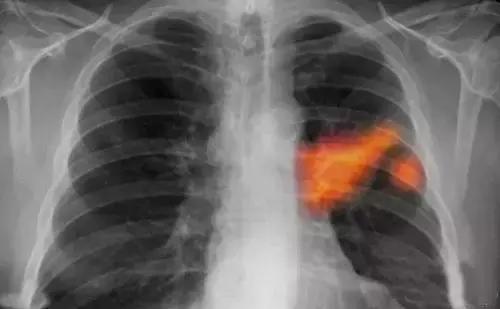

最近,浙二疼痛科连续碰到两位,因为肩痛来就诊的病人,原先都是当颈椎病在治疗,治疗效果不好,再检查,发现了肺癌,但病情着实也耽误了。

一位是老太太,78岁,肩膀痛,右胳膊麻。问诊的时候,老太太说的一个信息,引起了医生的注意:胸口痛,而且夜间特别明显。

医生给老太太开了个B超。检查结果,肺癌,颈部淋巴有转移。

另外一位病人要年轻得多,30多岁。颈肩痛,起先在其他医院就诊,拍片显示的确有颈椎病,但是治疗了一段时间效果不好,又来看专门的疼痛科。

跟老太太一样,这位病人也描述,肩背部的痛,晚上睡觉时会明显加剧,有时会被痛醒。他还告诉医生,当时医生还给他拍了胸片,说肺部有阴影,但他没有做进一步检查。

在浙二,医生又他做了CT,很快确诊了,也是肺癌。

浙二疼痛科的陈群山医生告诉钱报记者,碰到肩膀痛,做医生的心里都有根弦:是不是肺癌?

“一种情况,肿瘤长在上部,牵拉胸模可能引起肩膀痛;另一种情况,转移到锁骨、颈部、腰椎,压迫神经,也会引起手麻、腰背痛。”他解释说,因为这种疼痛不典型,所以很多病人往往经历了很多治疗、检查后才发现罪魁祸首是肺癌。